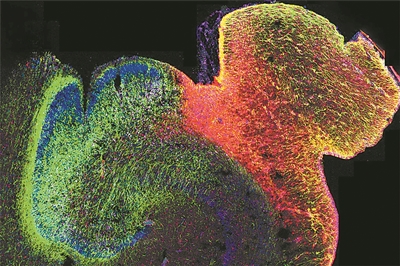

正在发育的人类海马体的荧光图像。图片来源:美国加州大学旧金山分校

科技日报北京10月9日电 (记者张佳欣)由美国加州大学洛杉矶分校牵头的一项研究,揭示了人类大脑发育过程中基因调控的演变方式,并展示了染色质的3D结构在其中发挥的关键作用。研究人员绘制了海马体和前额叶皮质中DNA修饰的首张图谱,这两个大脑区域对学习、记忆和情绪调节至关重要,也常与自闭症和精神分裂症等疾病相关。这项研究为早期大脑发育如何影响身心健康提供了新的见解。相关研究9日发表在《自然》杂志上。